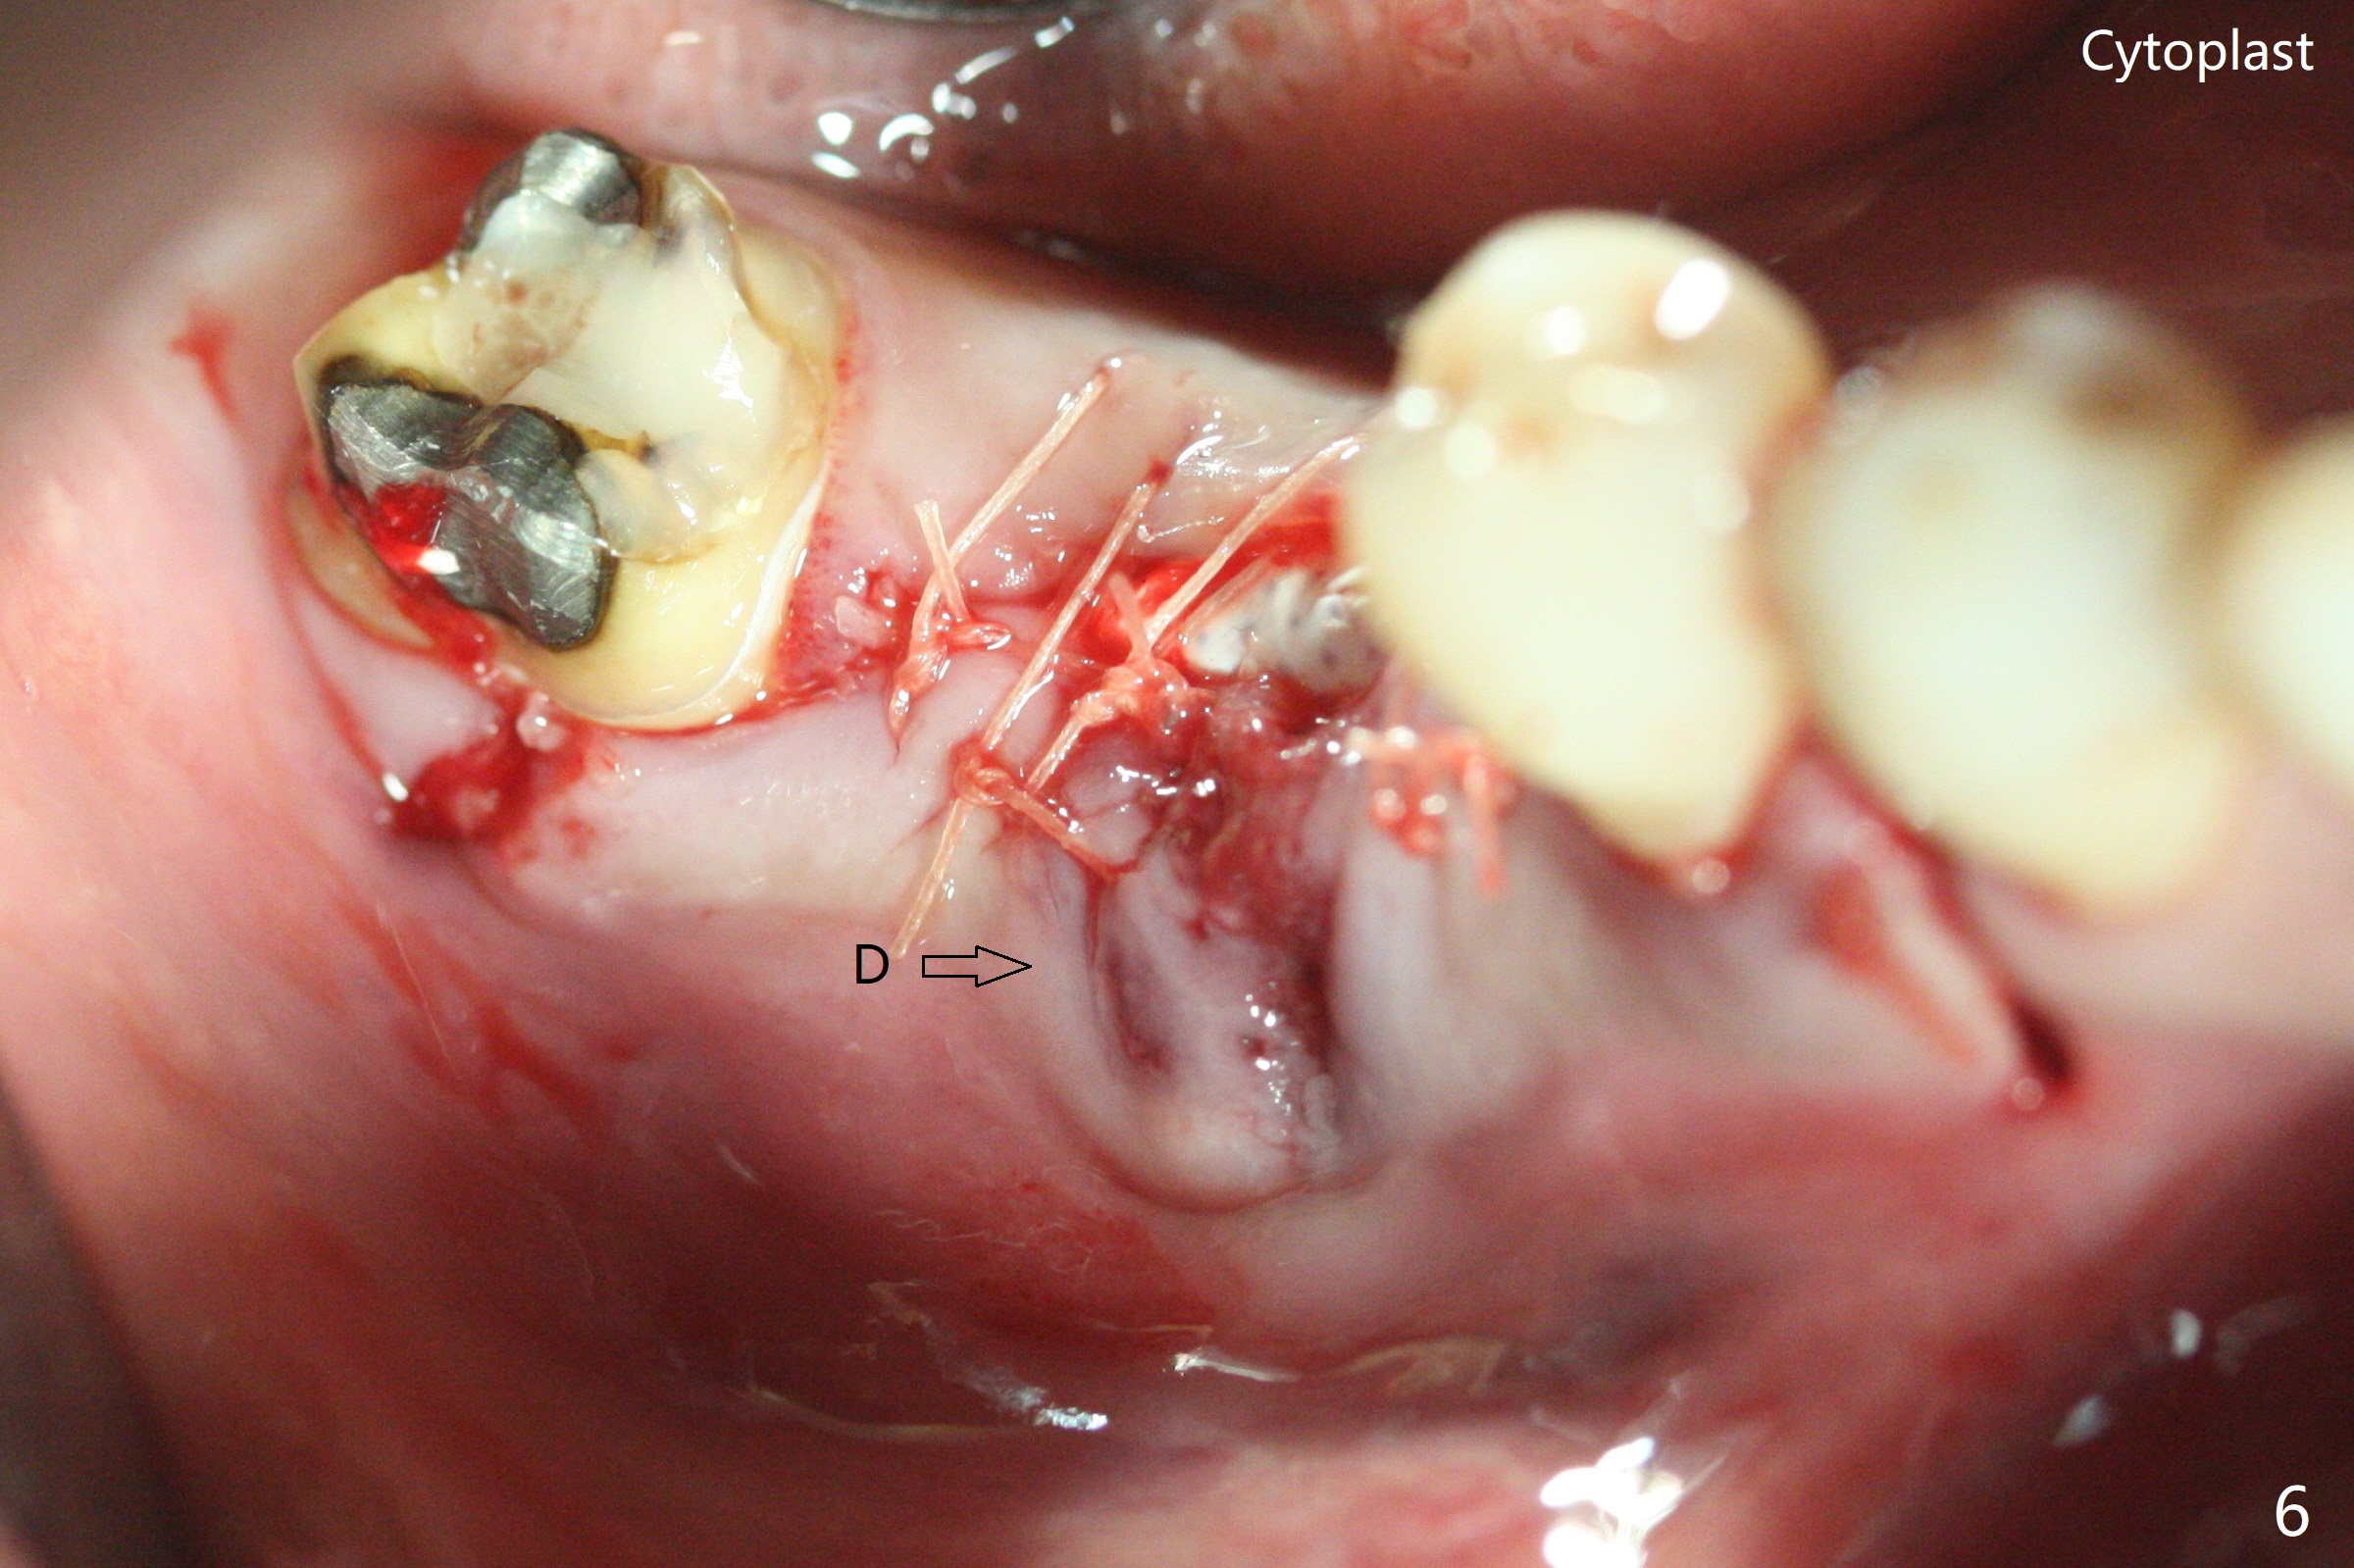

In spite of use of water pik, the coronal threads of the implant at #30 remain exposed 2 months postop (Fig.1). Envelop incision with mesial and distal accessory release ones reveals buccal bony defect (Fig.2). After 2nd spin (1500 RPM for 10 minutes), PRF forms in the red tube (Fig.3 yellow gel-like). Following use of Titanium brush, sticky bone is place (not so bone block-like, Fig.4), followed by a large piece of PRF membrane (from the red tube of Fig.3), Cytoplast (Fig.5,6 white porous) and a small piece of PRF membrane (from the white tube, next to the thin gingiva). The distal (Fig.6 D) and mesial (Fig.7 M) flaps are approximated (arrows without suture) as much as possible as well as lingual. 4-0 Polyglycolic Acid suture is used. Periodontal dressing dislodges 5 days postop. When the patient returns 1 week postop, he is pain free. Although Cytoplast is exposed, the surrounding gingiva seems to be healthy (Fig.8). Later the permanent crown of #31 is temporarily cemented with OHI. It appears that Cytoplast could be used to cover PRF membranes for soft tissue defect, followed by immediate provisional at the stage of immediate implant. The discolored (apparently contaminated) Cytoplast seems to be expelled 6 weeks postop (Fig.9). When the latter is removed, the soft tissue looks normal (Fig.10). Two weeks later, the apparently normal, but thin gingiva forms over the former granulation tissue (Fig.11 *, as compared to Fig.10). There is not enough bone coronal to the implant plateau 2 months post graft (Fig.12). Three months later, bone graft will be re-placed possibly with uncover.